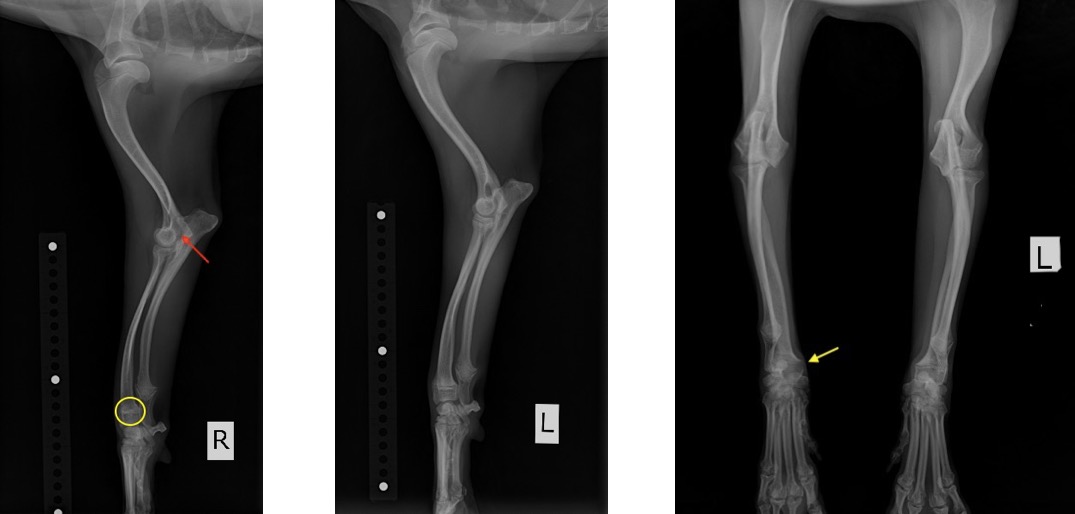

1ヵ月前から右前肢を挙上させたり、歩行時における負重の低下を主訴に来院されました。

院内においても右前肢の挙上が認められ、単純X線画像検査を実施したところ、右側の橈骨遠位成長板領域の不透過性亢進、肘突起と上腕骨顆の間隙が広がっている所見が認められたため、橈骨遠位成長板早期閉鎖が疑われました。

この症例では、反対側と比較して橈骨の湾曲が顕著でなかったため、肘関節の整合性を優先し、尺骨の骨切りを実施しました。

前腕の側面像と頭尾側像 (黄丸と黄矢印:成長板の不透過性亢進 赤矢印:上腕骨顆と肘突起の間隙)